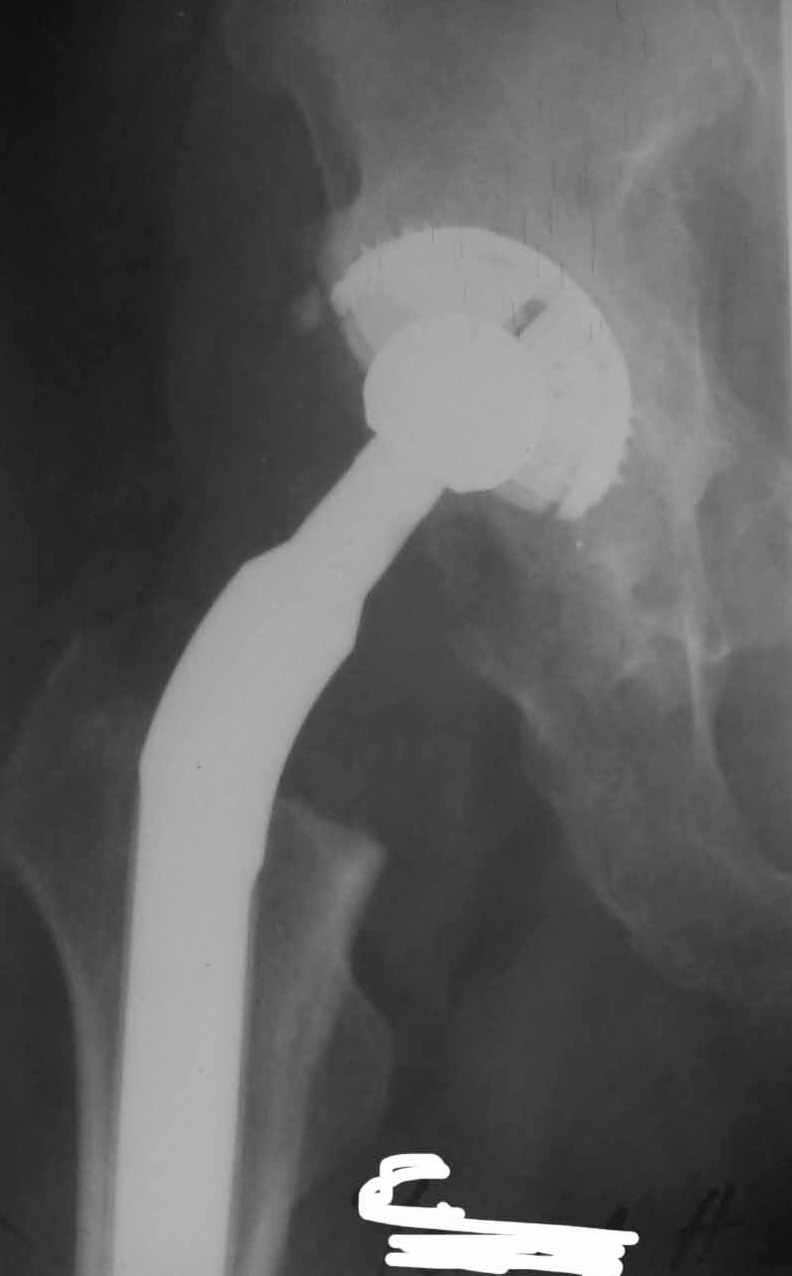

Дорогие коллеги.Мой хороший товарищ, сам травматолог-ортопед, прооперирован 1,5 мес назад. Естественно, начались проблемы. Хотелось бы узнать ваше мнениеи, главное,что делать дальше... Итак:Мужчина 50 лет.Д-з: Посттравматический деф.артроз правого тазобедренного сустава с выраженным болевым синдромом, стойкой комбинированной контрактурой иукорочением 3 см. Анамнез: 10 лет назад - сочетанная травма головы, груди, конечностей, таза... перелом заднего края вертлужной впадины и вывих бедра справа.Лечился консервативно. 25.05.94 - операция тотальное эндопротезирование правого тазобедренного сустава бесцементным эндопротезом (чашка Споторно 52, ножка Вагнера 225/21, головка L), дополнительная фиксация в кокситной гипсовой повязке в течение 3 нед. Спустя месяц после операции при поворачивании на бок в кровати произошел вывих головки эндопротеза. Под наркозом вывих вправили. Вот 10 дней лежит в постели. Что необходимо делать? Рентгенограммы до операции и после. Рентгенограммы в положении вивиха у меня отсутствуют. Ну наверное они и не столь важны, ведь вывих-то вправили. Учреждение и фамилию пациента, нашего коллеги, называть не буду. Он попросил меня собрать мнения - как ему жить дальше. Заранее благодарен. С уважением Александр Артемьев

Первые впечатления:

1. Вертикальное положение чашки;

2. Нарушение угла антеверсии ножки (судя по изображению малого вертела

на послеопреационной рентгенограмме).

3. Комбинация этих двух причин.

4. Видимо, тенденция к вывиху была уже на столе - вот Вам и кокситная повязка с надеждой на фиксацию протеза рубцом.

Сан Саныч,

Консультировать вывихи по рентгенограммам, не зная хода операции, дело не очень благодарное. Я думаю, что с датой операции Вы ошиблись и это был 2004 год? Тем не менее. Настораживают два фактора. Первое - не видно большого вертела. Если с мышцами обошлись грубо и их отсекли, то это очень грустно и нужна "связанная" пара, т.н. "constrain cup". Смущает хорошо прослеживаемый малый вертел и небольшая ретроверсия чашки. Возможно это (избыточная ретроверсия ножки и чашки) могло послужить причиной вывиха. Обычно гипсовая повязка после операции не накладывается, значит, были глубокие сомнения у оперировавшего хирурга. В этом случае - ревизия с перестановкой как минимум - ножки, а как максимум - обоих компонентов.

1. AP X ray of the Pelvis is a must. It will likely show that right hip/ femur is longer than left. Even based on Rt Hip AP X Ray it is my impression.

2. 2. Acetabular component is not vertical but rather anteverted, and also small ( small size was likely used because of the deficient posterior wall of the acetabulum).

3. Femoral component is malaligned relatively to the acetabular and combination of this factors (head is also small for this patient) is the reason for dislocation.( was likely anterior)